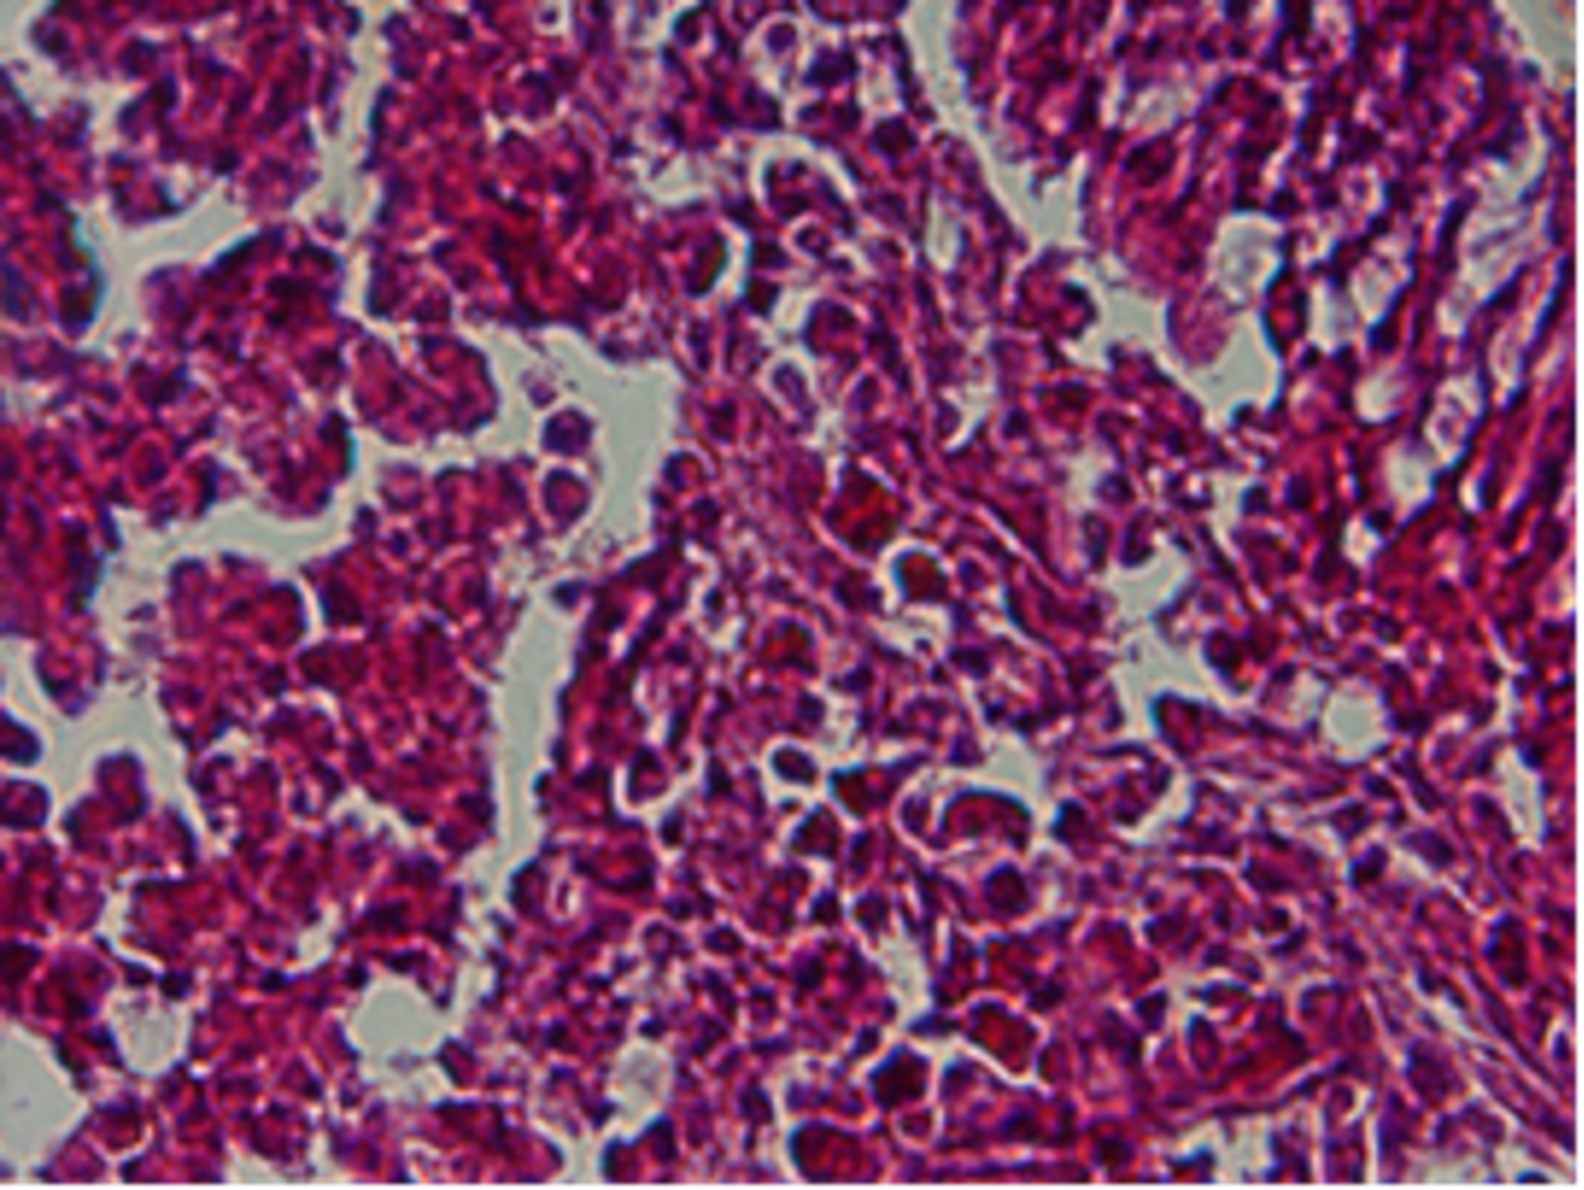

Infiltrasi Limfosit dan Makrofag di Lamina Propria dari Ileum Ayam Pedaging dengan Penambahan Aloe Vera pada Pakan

Aloe vera adalah salah satu fitofarmaka yang dapat digunakan sebagai imunomodulator. Khasiat lidah buaya sebagai obat herbal telah diketahui sejak 1500 sebelum masehi. Pengaruh pemberian lidah buaya pada pakan ayam pedaging terhadap infiltrasi makrofag dan lmfosit pada lamina propria ileum diamati melalui pemeriksaan preparat histologi ileum. Hewan coba yanng digunakan adalah 32 ekor ayam pedaging yang dibagi dalam 8 kelompok perlakuan yang terdiri dari 2 group kontrol, 3 kelompok perlakuan kering dengan dosis 0,5%, 1% dan 1,5%; serta 3 kelompok perlakuan basah dengan dosis 0,5%, 1% dan 1,5%. Data yang diperoleh diuji dengan Anova pola faktorial dilanjutkan dengan uji Duncan. Pada penelitian ini tidak didapatkan interaksi antara bentuk (kering dan basah) Aloa vera namun memberikan pegaruh terhadap jumlah limfosit lamina propia ileum pada perbedaan pemberian dosis. Penambahan Aloe vera tidak mengakibatkan peningkatan jumlah makrofag lamina propria namun diguga berperan dalam aktivasi kerja dari makrofag. Berdasarkan hasil penelitian, dapat disimpulkan bahwa Aloe vera dalam bentuk kering dan basah dengan menggunakan tiga tingkatan dosis pada ayam pedaging dapat meningkatkan infiltrasi limfosit di lamina propria dari ileum tanpa mempengaruhi jumlah infiltrasi makrofag.